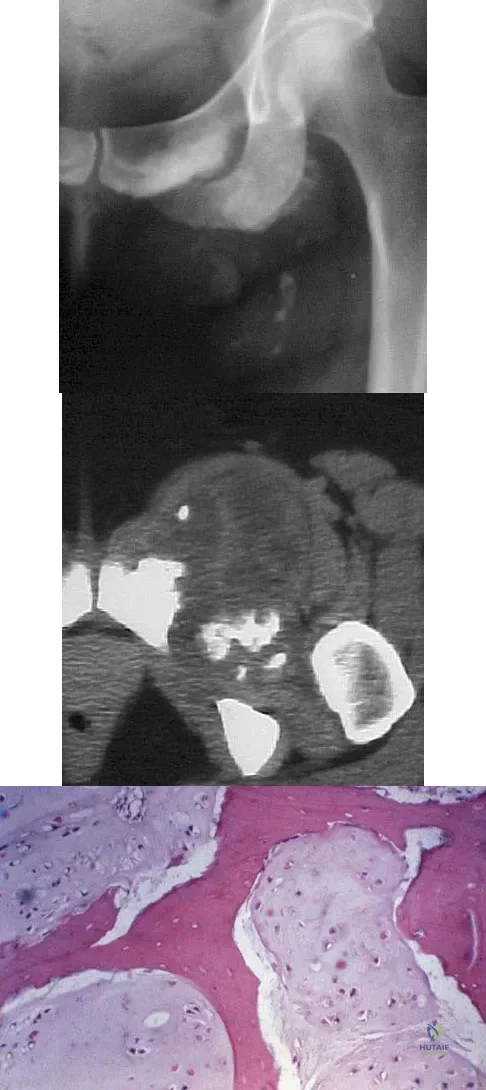

Question 23

A 43-year-old woman has an enlarging mass in the left groin. A radiograph, CT scan, and a biopsy specimen are shown in Figures 42a through 42c. Treatment should consist of

Explanation